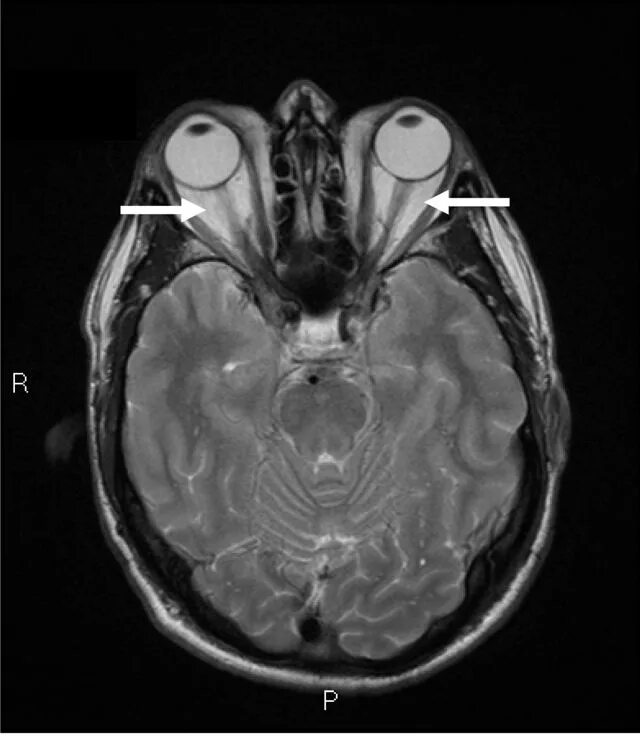

Томограмма глаза